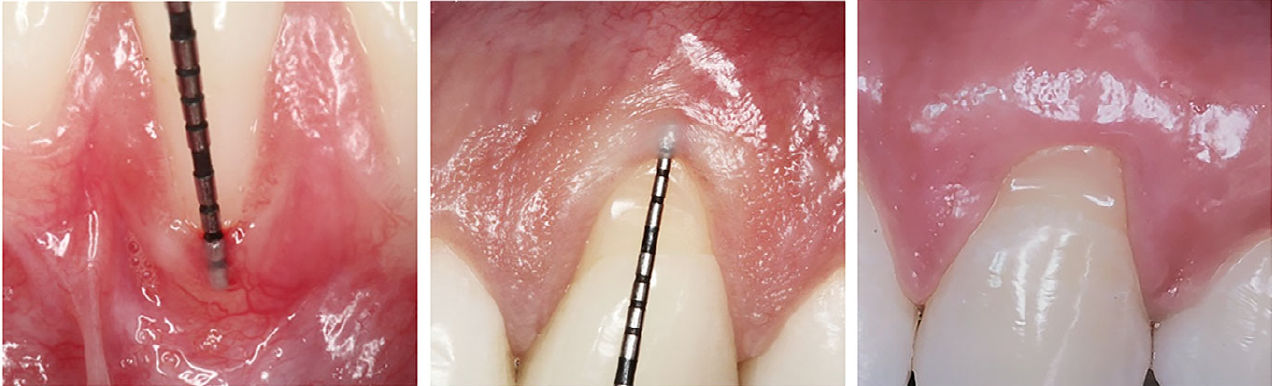

Типичный случай рецессии десны RT1 и NCCL типа B+ с 7-летним периодом наблюдения

Рис 3. Типичный случай рецессии десны RT1 и NCCL типа B+ с 7-летним периодом наблюдения. (A) Исходная картина комбинированного дефекта (CD). (B) Реконструкция пришеечной части NCCL по реставрационному протоколу CEJ+1 мм. Обратите внимание на плавный профиль выхода. (C) Вид через 1 год после выполнения коронально смещённого лоскута (CAF) в сочетании с CTG. Отмечается фестончатый контур десневого края. (D) Стабильность результата через 7 лет наблюдения

Типичный случай V-образного некариозного пришеечного поражения

Рис 4. Типичный случай V-образного некариозного пришеечного поражения (NCCL). V-образные поражения обычно характеризуются выраженной вестибуло-пульпарной глубиной при ограниченной апико-коронковой высоте, часто с соотношением глубины к высоте, близким к 1. Частичные реставрации при таких NCCL могут быть нецелесообразны